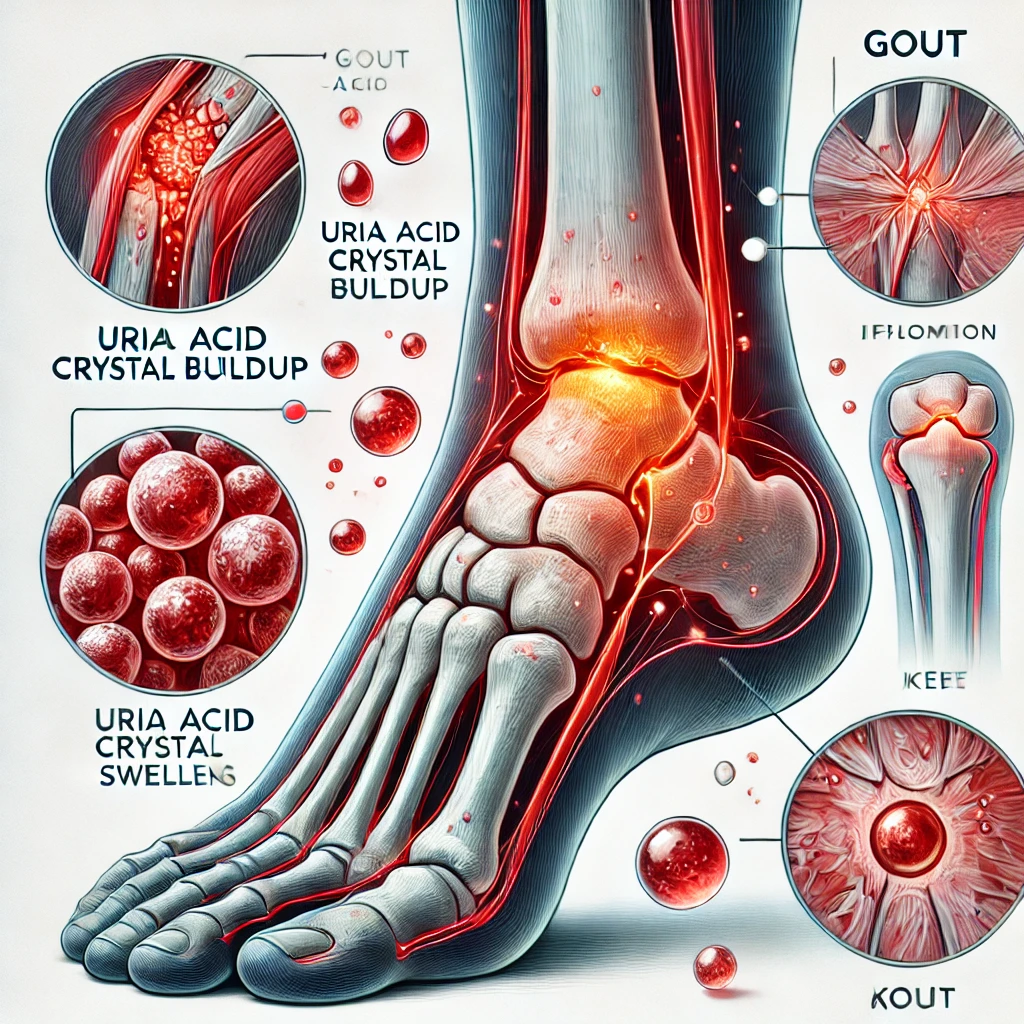

Gout

Gout is a form of inflammatory arthritis characterized by sudden, severe

pain, redness, swelling, and tenderness in the joints, often affecting the big toe. It

occurs when uric acid crystals accumulate in the joints due to elevated levels of uric

acid in the blood, a condition known as hyperuricemia.